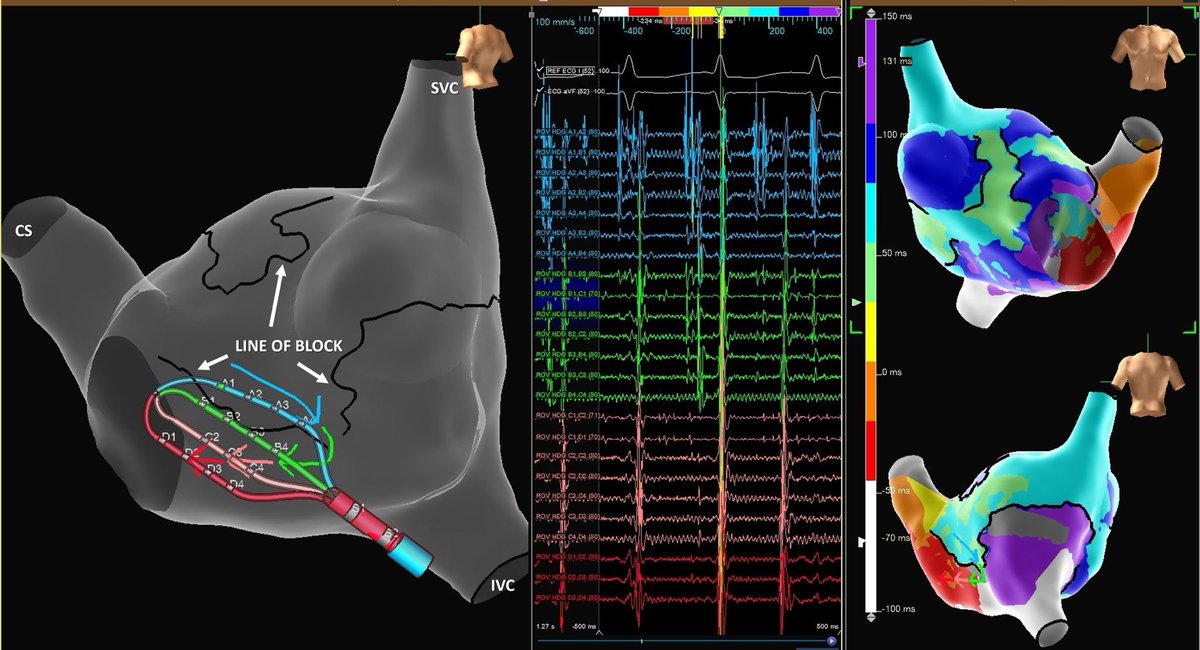

Unipolar Peak-Negative mapping paired with Last Duplicate point projection provides real-time feedback of regional q wave elimination during ablation. Signal clarity, brought to you by #TactiFlex

3rd Time REDO AF / Atypical Flutter. 80k Omnipolar points mapped in minutes using HD Grid and Ensite X which led to a clear ablation strategy and a nice result. 1🔥term. #AbbottMapsOhio #MidAmericaEP @EPCece @AbbottCardio